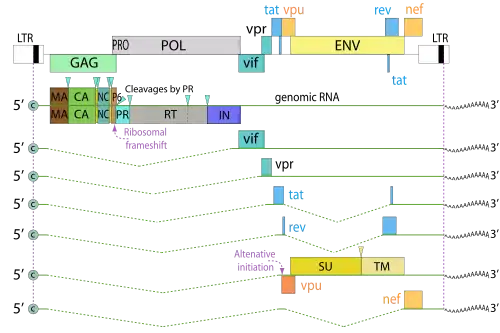

Das HIV gehört zu den komplexen Retroviren, das heißt, die Viren besitzen neben den kanonischen retroviralen Genen gag (gruppenspezifisches Antigen), pol (Polymerase) und env (envelope) weitere Leseraster, namentlich tat und rev (für regulatorische Prozesse) sowie vif, vpu, vpr und nef (für akzessorische Prozesse).[11] Durch die teils überlappenden offenen Leseraster können trotz der geringen Genomgröße (ca. 9.700 bp)[21] neun verschiedene Proteine kodiert werden.[11] Sogenannte LTR-Regionen (Long Terminal Repeat) befinden sich am 5'- und 3'-Ende, die u. a. die Transkription und Integration ins Wirtsgenom regulieren.

Das gag-Gen kodiert für die Strukturproteine p24, p17, p7 und p6, env für die Oberflächenproteine gp120 und gp41. Die Reverse Transkriptase, die HIV-Protease sowie die Integrase finden ihren Ursprung in pol.

Für die regulatorische Prozesse ist tat für die Initiierung der Transkription und rev neben der Bindung an das HIV Rev Response Element des Genoms (RRE) am Export viraler mRNA aus dem Zellkern in das Cytoplasma beteiligt.[11]

Die Expression verschiedene Rezeptoren und Antigene (zum Beispiel CD4, CD8, CD28, CD3, SERINC3/5, Tetherin und HLA-Klasse-I-Antigene) wird bei HIV-infizierten Zellen mittels nef herunterreguliert. Dies hat zur Folge, dass das Immunsystem solche Zellen schlechter erkennen und damit bekämpfen kann. Außerdem erhöht es die Replikationsrate von HIV in diesen befallenen Zellen, was die Infektiosität steigert.

Die antivirale Aktivität von APOBEC3G wird durch vif beeinträchtigt; APOBEC3G verursacht Mutationen in der viralen RNA und schädigt diese, es handelt sich um ein Element des Immunsystems zur Abwehr von Retrovirus-Infektionen. Vpr vermittelt den Transport des viralen Genoms in den Zellkern. Tetherin wird schließlich durch vpu gehemmt, infolgedessen werden gereifte Viren besser freigesetzt. Außerdem baut vpu CD4-gp120-Komplexe ab, wodurch env-Proteine freigesetzt werden, welche für Virionen benötigt werden.[11]

Das nun als integriertes Provirus vorliegende virale Genom zeigt einen charakteristischen Aufbau, wobei die codierenden Bereiche auf beiden Seiten von identischen regulatorischen Sequenzen, die im Verlauf der reversen Transkription generiert wurden, den sogenannten LTRs, flankiert sind. Der Promotor, unter dessen Kontrolle die Transkription der verschiedenen mRNAs erfolgt, liegt im Bereich des LTR und wird durch das virale Protein TAT aktiviert. Eine ungespleißte RNA dient als virales Genom für die nächste Generation von HI-Viren und als mRNA für die Translation eines Gag (Gruppenspezifisches Antigen) sowie mittels einer in einem von 20 Fällen vorkommenden Verschiebung des Leserasters eines Gag-Pro-Pol-Vorläuferproteins. Gespleißte RNAs codieren für das Hüllprotein Env sowie die ebenfalls im 3'-Bereich befindlichen weiteren Proteine. HIV codiert für 16 Proteine.[100]